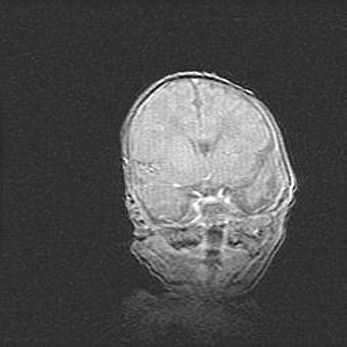

Открытая гидроцефалия.

Возраст: 6 месяцев 15 дней

Вес: 6200 г

Пол: женский

Окружность головы: 41 см

Срок гестации: 38 недель

Гидроцефалия головного мозга у новорожденных – это скопление избыточного количества цереброспинальной жидкости в головном мозге. Ее избыточное скопление в мозге приводит к патологическому расширению желудочков мозга (четырех полостей, расположенных в глубине белого вещества мозга, заполненных цереброспинальной жидкостью и связанных узкими проходами).

Открытый тип гидроцефалии (сообщающаяся) наблюдается тогда, когда нарушен механизм всасывания ликвора в системный кровоток. При этом типе причиной заболевания чаще всего является перенесенные ранее инфекции (например: менингит),  либо же наличие крови в субарахноидальном пространстве.